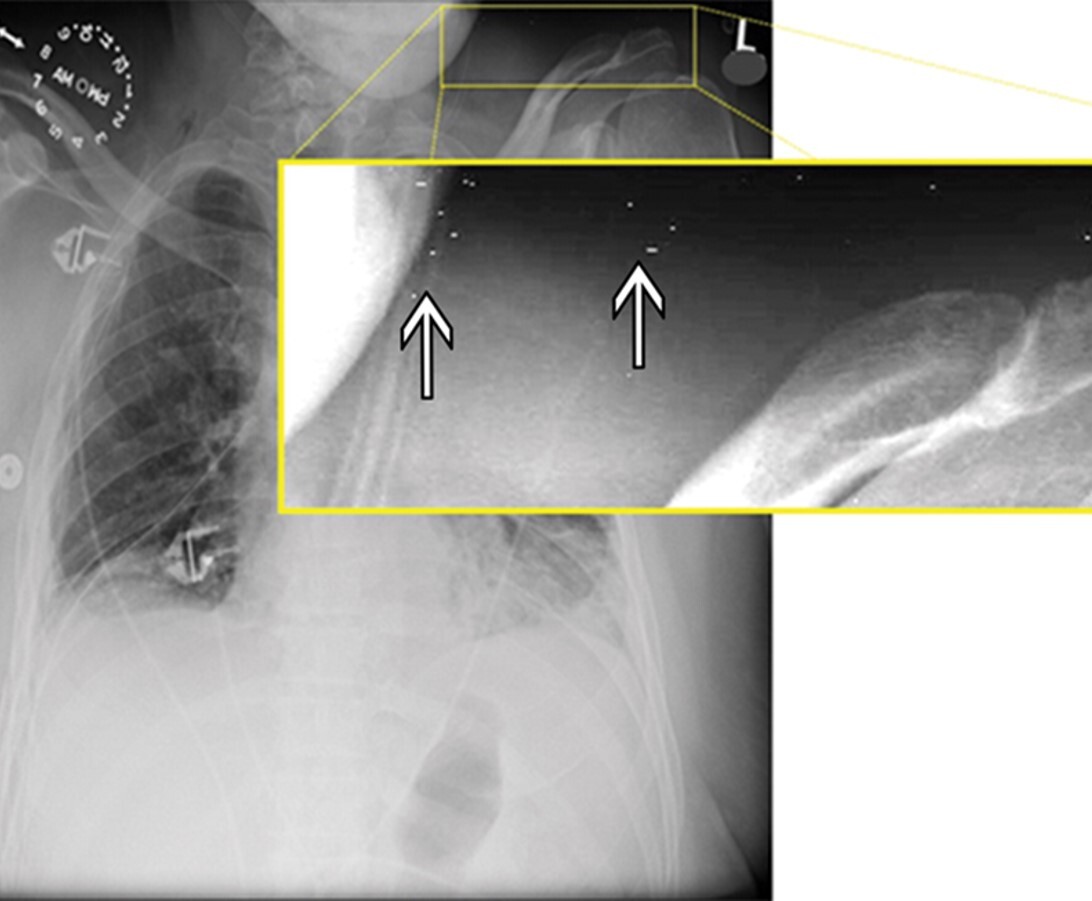

14

Q

What artifact is seen superimposed over the scapula and lateral chest wall in the attached image?

A

Patient artifact (bra straps)